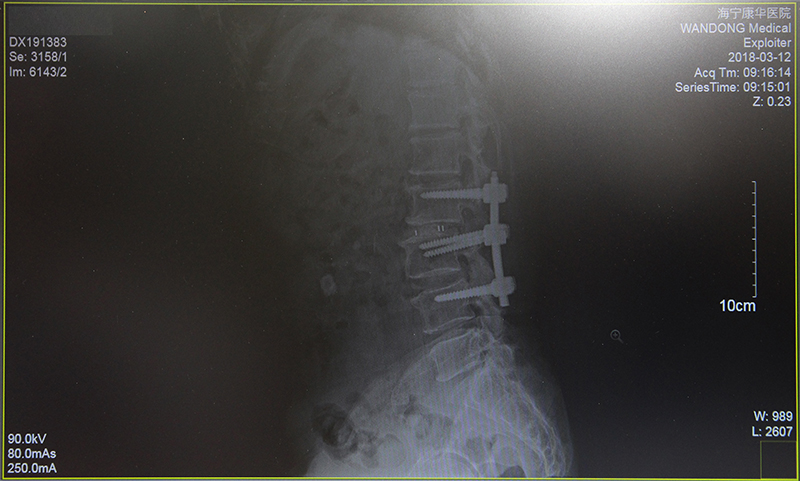

“大伯恢复得不错啊。”眼看沈大伯能流畅地自己行走,鲍立峰十分欣慰,“来,您先坐这里,我再看看您这次的片子。”调出电脑中前后两次的拍片记录,鲍立峰向沈先生解释大伯最新的骨骼状况,“钢钉位置挺好的,骨头正在慢慢长起来了。”

经过详细的术前检查与计划,2月2日,在鲍立峰主刀下,为沈大伯进行了“腰2/3,腰3/4减压术及腰2/3椎体融合术”。整台手术历时约3小时,较好地纠正了大伯多处突出的腰椎。第二天,沈大伯的左下肢已经恢复了肌力。随后,配合康复治疗等,两周后,大伯顺利出院了,此时的他已经基本可以靠着拐杖独立行走了。

(术前)

(术后)